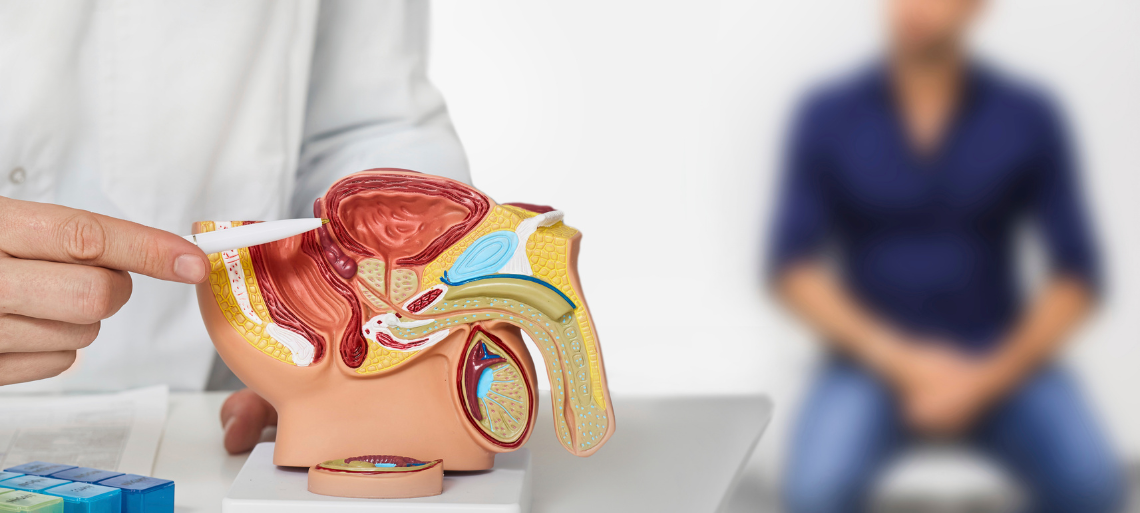

Prostate cancer is a type of cancer that develops in the prostate gland, a small gland in men responsible for producing seminal fluid. It is one of the most common cancers in men, particularly after the age of 50. When detected early, prostate cancer can be treated successfully with excellent long-term outcomes.

In its early stages, prostate cancer may not show clear symptoms. As the disease progresses, men may experience difficulty in urination, weak urine flow, frequent urination especially at night, pain or burning during urination, blood in urine or semen, pain in the lower back or hips, and erectile dysfunction. These symptoms may also occur due to non-cancerous prostate conditions, making medical evaluation essential.

Early and accurate diagnosis plays a crucial role in prostate cancer management. Diagnostic services include PSA (Prostate-Specific Antigen) blood tests, digital rectal examination, prostate biopsy, MRI and advanced imaging, and staging investigations for advanced disease. All diagnostic decisions are guided by experienced cancer specialists.